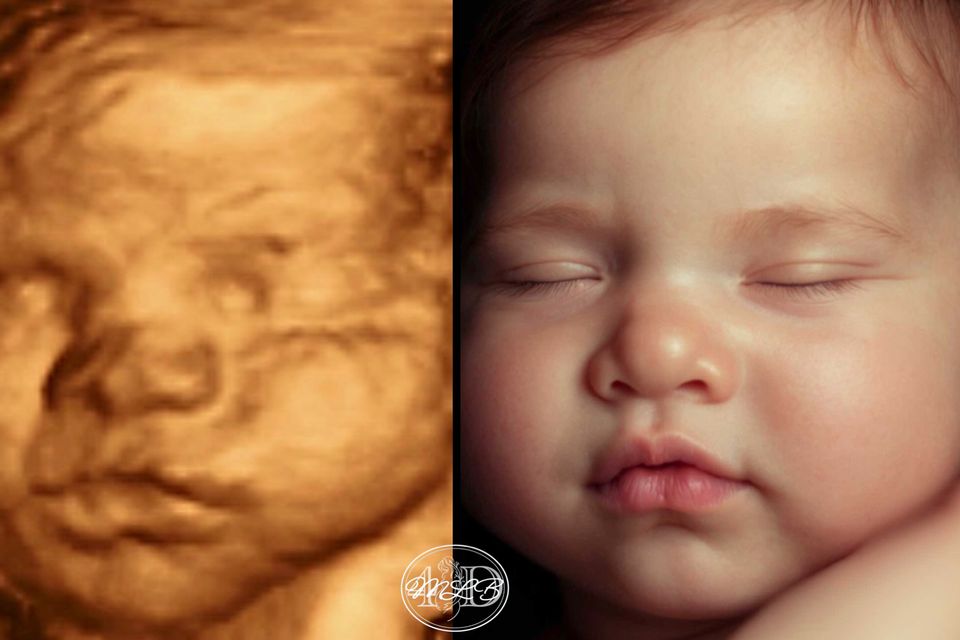

Most Realistic & lifelike photo you can get until the arrival of your little one. Using the newest technology to change your 3d/4d photo into something more realistic without changing any of your baby's features.